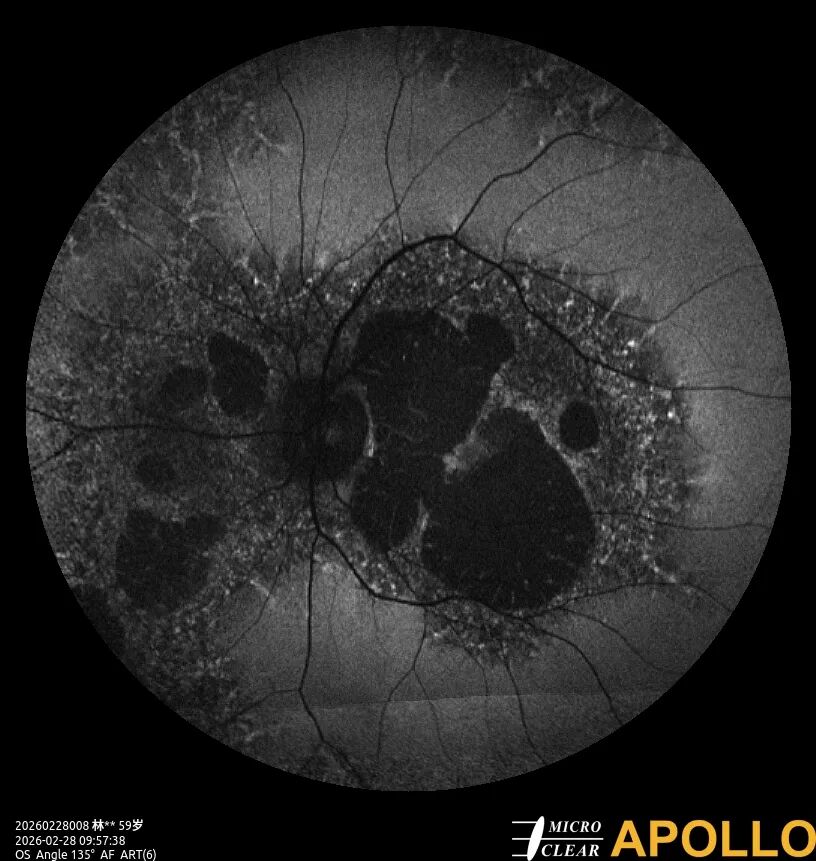

左图:Bietti黄斑营养不良 自发荧光

右图: Bietti黄斑营养不良